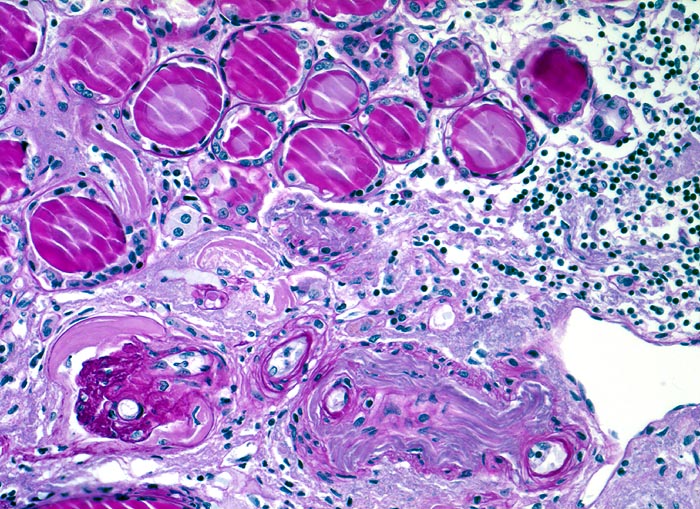

Histologisch finden sich neben völlig unverändertem Parenchym herdförmige Infiltrate aus Lymphozyten, Plasmazellen, Histiozyten und bei akutem Schub zusätzlich neutrophile Granulozyten. Das destruierte Gewebe wird durch Granulationsgewebe im Intersititum organisiert. Gruppen erhaltener Tubuli mit vergrössertem Durchmesser und abgeflachtem Epithel gefüllt mit Harnmukoid (=Tamm-Horsfall Protein und/oder IgA) bilden Pseudostrumaherde (> 1793). Diese sind ein wichtiger Hinweis aber kein Beweis für chronische Pyelonephritis. Bei Kindern finden sich oft zusätzlich Lymphfollikel. Glomeruli kollabieren und zeigen eine konzentrische periglomeruläre Fibrose. Oft findet sich eine Arteriolosklerose und eine adaptative Intimafibrose grösserer Arterien. Obligat findet sich eine schwere chronische Pyelitis sowie eine Fibrose von Nierenbecken und Nierenmark.

• Streifenförmige Narben mit Pseudostrumaherden (dilatierte sekretgefüllte (Tamm-Horsfallprotein +/- IgA) Tubuli mit abgeflachtem Epithel).

• Chronisches überwiegend lymphozytäres Entzündungsinfiltrat im Interstitium.

• Glomerula mit kollabierten Kapillarschlingen.